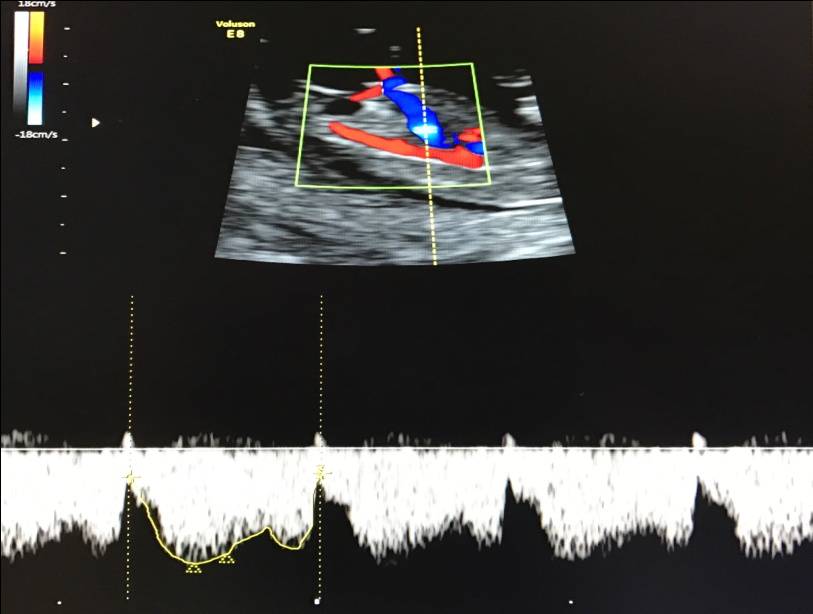

– кровоток в венозном протоке – это маленький сосуд в печени плода. При обратном (ретроградном) токе крови в данном сосуде можно предположить, что у плода хромосомный синдром, либо врожденный порок сердца.

Нормальный кровоток в венозном протоке

Но важно правильно получить этот кровоток и дать ему оценку. Для этого требуются определенные навыки и квалификация врача, которые подтверждаются ежегодной сертификацией FMF.. – кровоток через трикуспидальный клапан в сердце плода

Здесь ретроградный (обратный) кровоток тоже указывает на хромосомную патологию, либо может проявляться при врожденных пороках сердца.

– кровоток через трикуспидальный клапан в сердце плода. Здесь ретроградный (обратный) кровоток тоже указывает на хромосомную патологию, либо может проявляться при врожденных пороках сердца.